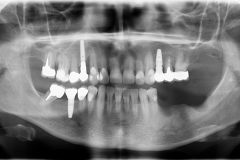

• radiografie panoramiche